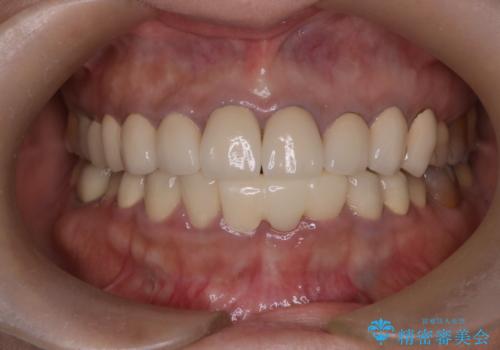

前歯が一本取れた オールセラミックブリッジによる補綴治療

抜歯をしているため、その部位の治癒を待ってからブリッジを装着するので、2-3か月ほど治療期間を必要としました。